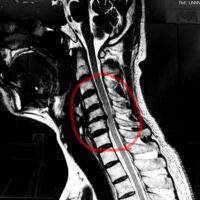

2回目の施術日の前日に整形外科でMRI撮影。かなりひどい腰椎椎間板ヘルニアであることが分かった。

画像を確認したところ、かなり重度の腰椎椎間板ヘルニアが認められました。

赤〇の箇所は、椎間板が後方に飛び出ており神経を圧迫している様子がよくわかります。